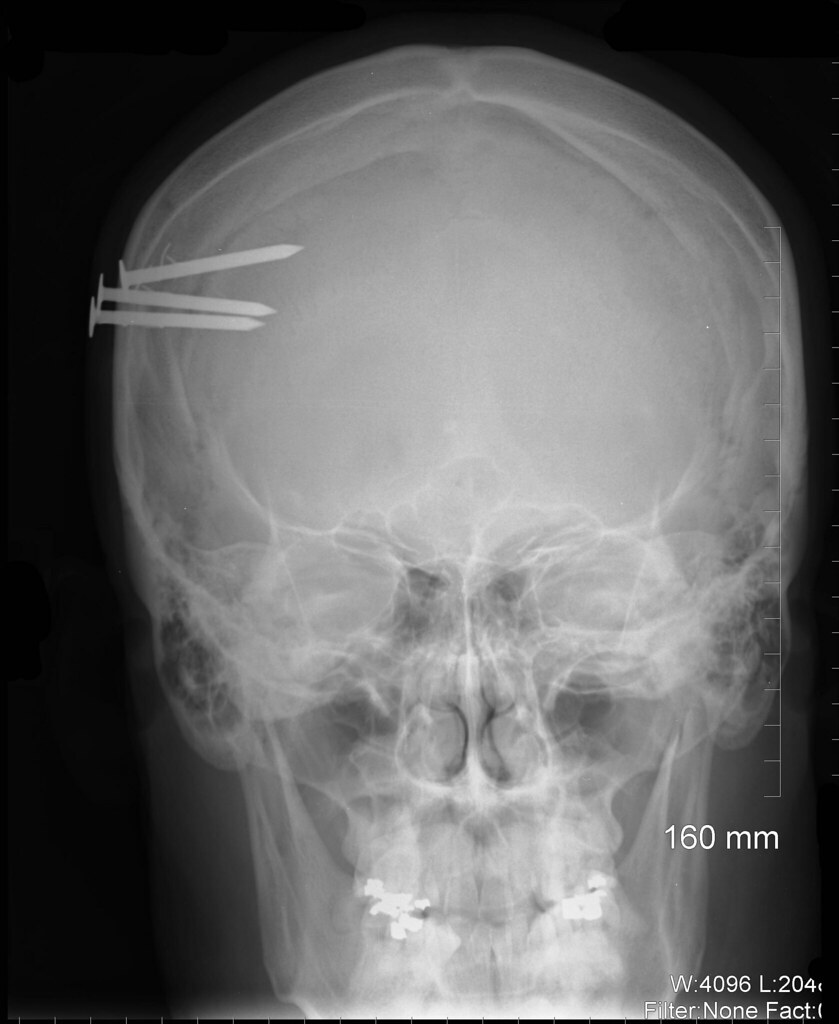

Nail Gun X Ray Head . Nail gun injuries to the head are an extremely rare form of neurotrauma with a relatively low mortality and morbidity compared with high. Due to its rare occurrence, clinical judgement of the neurosurgeon directs immediate and ongoing management. Brain computed tomography (ct) showed the presence. Mortality and morbidity is low for surgically managed isolated nail gun. In the patient with head injury by pneumatic nail gun, the first evaluation should focus on the shape of the nail head and vascular. Nail gun injuries can present with variable clinical status; Nail gun injuries involving vital organs, especially those involving the brain or heart, often result in severe wounds and require.

Nail gun injury Radiology at St. Vincent's University Hospital Nail Gun X Ray Head In the patient with head injury by pneumatic nail gun, the first evaluation should focus on the shape of the nail head and vascular. Nail gun injuries to the head are an extremely rare form of neurotrauma with a relatively low mortality and morbidity compared with high. Nail gun injuries involving vital organs, especially those involving the brain or heart,. Nail Gun X Ray Head.